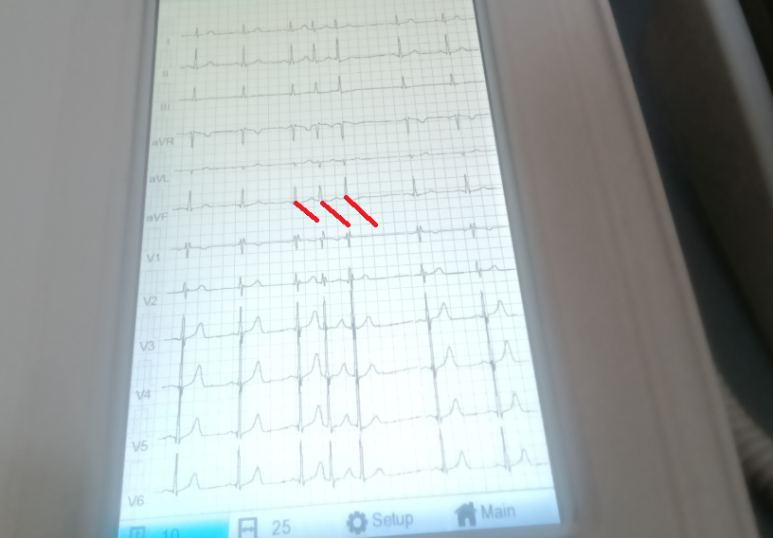

특직정이지 않은 흉통 기술의 확인, 협심증은 아니라 보아 약제 중단 후 추적, 부정맥은 기외수축 이상의? 평가가 필요 - 동대문구 답십리, 용답동, 우리안애 우리안愛 내과

60대 초반 여자, 초진 친구의 추천을 받고? 복용하는약: 헤르벤서방캡슐180mg, 시그마트정5mg, 스토마정, 아테놀정, 로수엠젯정10/5mg, 가스프렌정, 넥시리움정20mg - *내과 2024년 발한과 가슴이 조이는 증상으로 의원에서 - 이때도 수초간?? 진료의가 협심증이라고.. ; 그때만, 이후로 조이는 증상은 없었고... 가끔씩 건너띄는 느낌.. ; 기외수축이 있을지? 가끔 뜨끔하다. 1~2달에 한번.. 뜨끔... ; 이건 부정맥 증상도 아니고 precordial catch에 해당하는 기술로 봐도... 간헐적 맥박으로 **대 응급실, 25년... 외래에서 처방은 있었으나 홀터는 달지는 않았고... ; 검사에 응하지 않고... 매달 1~2회, 하루에 잠깐... ; 기외수축으로 봐도 될지? 진료실 혈압 132/60 - 맥박은 규칙적 일상생활/작업 (식당)/버스잡으려고 뛸때 등에서 증상 유발은 없으며... 노작성 흉통 (전형적 흉통